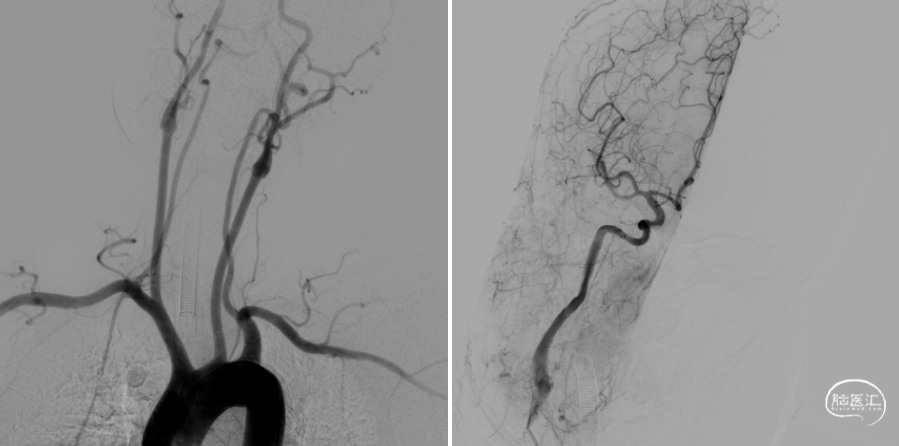

术前造影提示右侧大脑中动脉下干闭塞。

使用8F导引导管在6F 125cm Tethys®中间导引导管同轴下超选至右侧颈内动脉建立通路,造影可见右侧大脑中动脉M1下干闭塞。

Tethys®中间导引导管到达大脑中动脉血栓部位,边抽边撤Tethys®中间导引导管,未见血栓;Tethys®中间导引导管再次到位大脑中动脉,微导丝微导管通过闭塞段,微导管造影证实在真腔。

释放3*25mm Syphonet®取栓支架,停留5分钟后撤出Syphonet®取栓支架并保持负压抽吸,第一次复查造影血流未通。

再次重复上述操作,释放Syphonet®取栓支架并停留5分钟后撤出取栓支架并保持负压抽吸,再次复查造影右侧大脑中动脉下干血流恢复,mTICI血流3级。